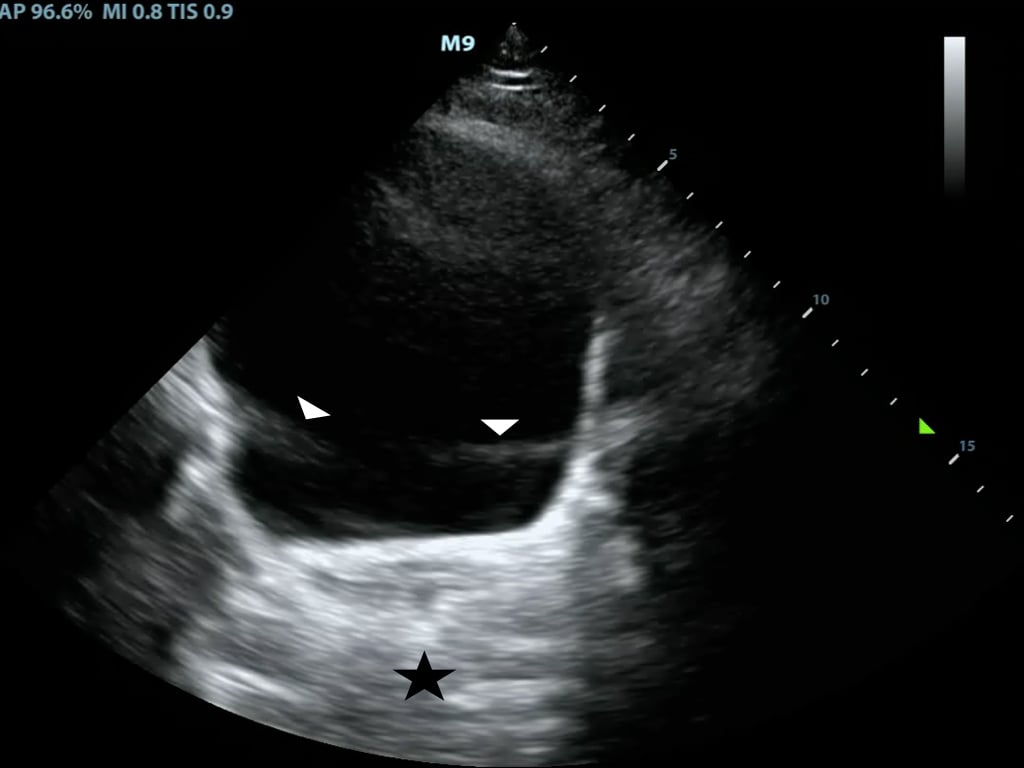

- In posterior enhancement, the area behind an echo-weak or echo-free structure appears brighter (more echogenic) than its surrounding structures

- Neighboring signals must pass through more attenuating structures and return with comparatively weaker echoes

- A common place for this to occur is posterior to the anechoic bladder (Figure 8)

- Figure 8. Posterior acoustic enhancement deep to the bladder and side lobe artifact